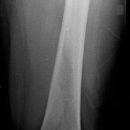

Oberschenkel

Oberschenkel a.p.

Patient in Rückenlage, Bein leicht abgespreizt, Fußspitze nach innen rotiert.

Senkrecht auf Oberschenkelmitte d.h. Femur

1. proximaler Oberschenkel: mit Darstellung der Hüfte, oberer Kassettenrand 2 QF oberhalb der Spina bzw. Lichtvisier bis Spina.

2. distaler Oberschenkel: mit Darstellung des Knies, unterer Kassettenrand 4 QF unterhalb der Patella.

Qualitätskriterien

Bei Erwachsenen soll das Hüftgelenk a.p. orthograd mit abgebildet sein. Bei distaler Aufnahme muss das Kniegelenk orthograd getroffen werden.